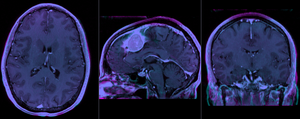

Registration Results

RegLib C01 unregistered.png baseline and follow-up before registration (click to enlarge)

RegLib C01 rigid.png after rigid alignment. Note the residual shape differences (click to enlarge)

RegLib C01 affine.png after affine registration (click to enlarge)

• The affine registration seeks to address residual distortions that are typical for longitudinal MRI. However to prevent the tumor (and putative tumor change) from affecting the registration, we mask out the tumor so that it does not contribute to the registration. The assumption is thus that aside from the tumor we expect the two serial scans to be matching exactly, i.e. any differences in size or shape is considered an artifact we wish to remove by registration.